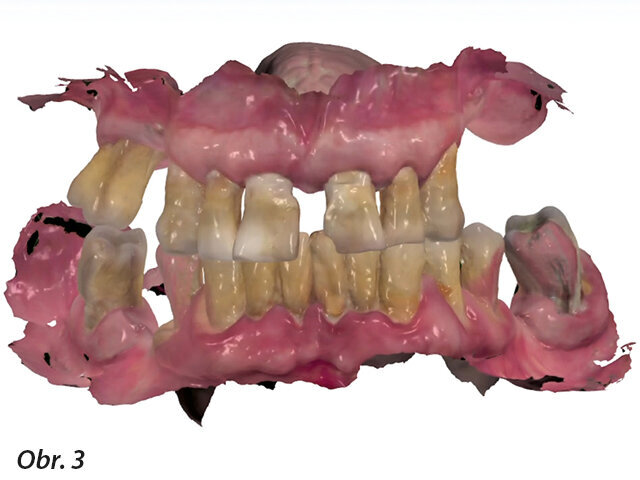

Před zahájením operace byl proveden intraorální sken k zaznamenání výchozí situace a odeslán do laboratoře jako pacientův původní stav (soubor 1). Tento soubor obsahoval všechny informace týkající se předoperační situace pacienta, včetně zubů, estetiky, výšky skusu a okluze (obr. 3). Operace byla prováděna v lokální anestezii a také s pomocí vědomé intravenózní sedace midazolamem za dohledu anesteziologa a monitoringu pacienta pulzní oxymetrií.